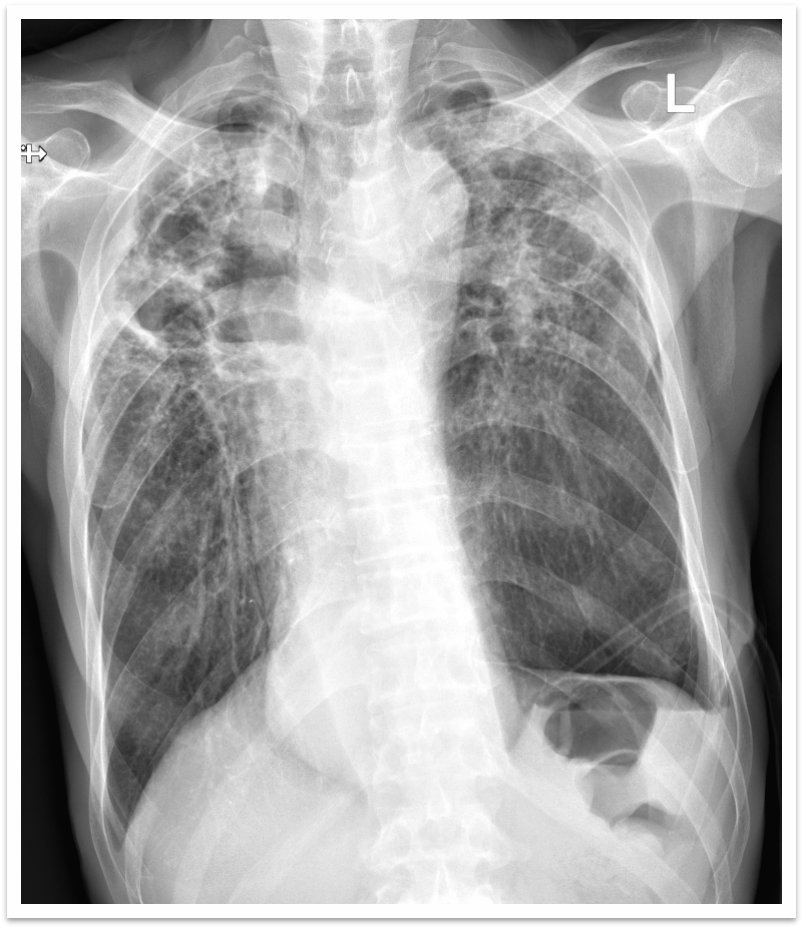

第一台局麻手术:患者老年男性,既往有COPD病史多年,因为信赖,长期就诊于我院胸肺疾病研究所—呼吸与危重症及睡眠医学科门诊,近期再次胸闷憋气,当听说医院复诊,第一时间来我院就诊,胸片提示左侧气胸,为患者急诊行胸腔闭式引流手术,术后,患者胸闷、胸痛症状得到明显缓解。

手术前胸片